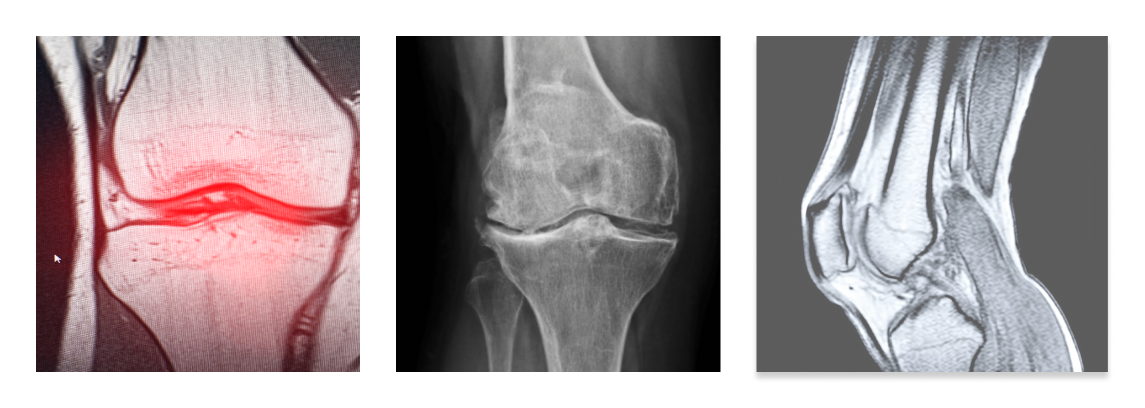

Lo specialista si avvale di esami strumentali per valutare l’entità e il grado di artrosi: esame radiografico, TC e/o RMN. In presenza di cospicui versamenti articolari si procede all’aspirazione del liquido sinoviale.